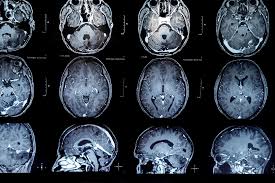

Erol, açıklamasında "Bilimsel çalışmalar gösteriyor ki 120’ye yakın beyin tümörü tipi var. Beyin tümörleri beyin hücrelerinden kaynaklanan birincil tümörler ve diğer organlardaki kanserlerin beyne yayılmasıyla oluşan tümörler olarak ayırıyoruz. Bazen kafa travmaları, bazen kalıtsal özellikler, bazen de maddelere veya radyasyona maruz kalma gibi etkenlerle oluşabiliyor. Bazı hastalıklarla beraber beyin tümörlerini görmek mümkün.” ifadelerine yer verdi.

Tanı için hastanın öyküsü, şikayetlerinin dinlenmesi ve sonrasında fizik muayene ve görüntüleme yöntemlerinin büyük önem taşıdığını ifade eden Erol, "Tanıyı koyduktan sonra birçok beyin tümörünün tedavisi cerrahi müdahale ile yapılıyor. Bazan gerekli durumlarda biyopsi alınıp sonra tedavi basamaklarına geçiliyor. Cerrahi tedaviden sonra kemoterapi, radyoterapi veya radyo cerrahi gibi ek tedaviler uygulanabiliyor. Bazen de hiçbiri yapılmayıp sadece takipler ile beyin tümörünün tedavisi yapılabiliyor." ifadelerini kullandı.